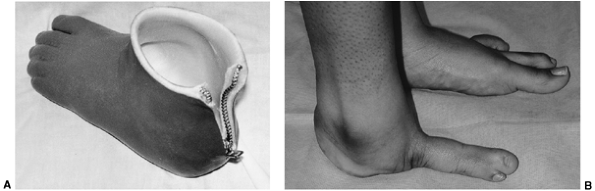

In the Boyd amputation, the talus is excised and the retained calcaneus

with the heel pad is arthrodesed to the tibia. The surgery was

initially devised to avoid the complication of posterior migration of

the heel pad seen in some children with Syme amputation. However, the

main complication of the Boyd amputation is the migration of the

calcaneus if arthrodesis is not achieved. This requires an additional

surgery, which is often conversion to a Syme amputation. An advantage

of the Boyd amputation is that with the retained calcaneus, the heel

pad tends to grow with the child, rather than remaining small as in the

Syme amputation. The Boyd amputation also adds length. This can be a

problem when children who do not have significant shortening of the

limb are fitted for various prosthetic feet and may require a shoe lift

on the normal side.